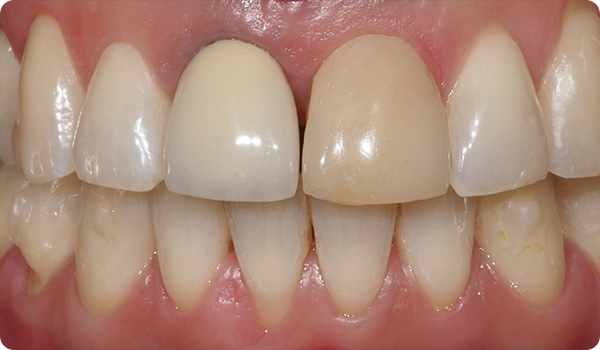

Het uitlijnen van de tanden met Right is de perfecte en meest conservatieve basis voor toekomstige whitening of fineerbehandelingen die de glimlach van de patiënt perfect maken.